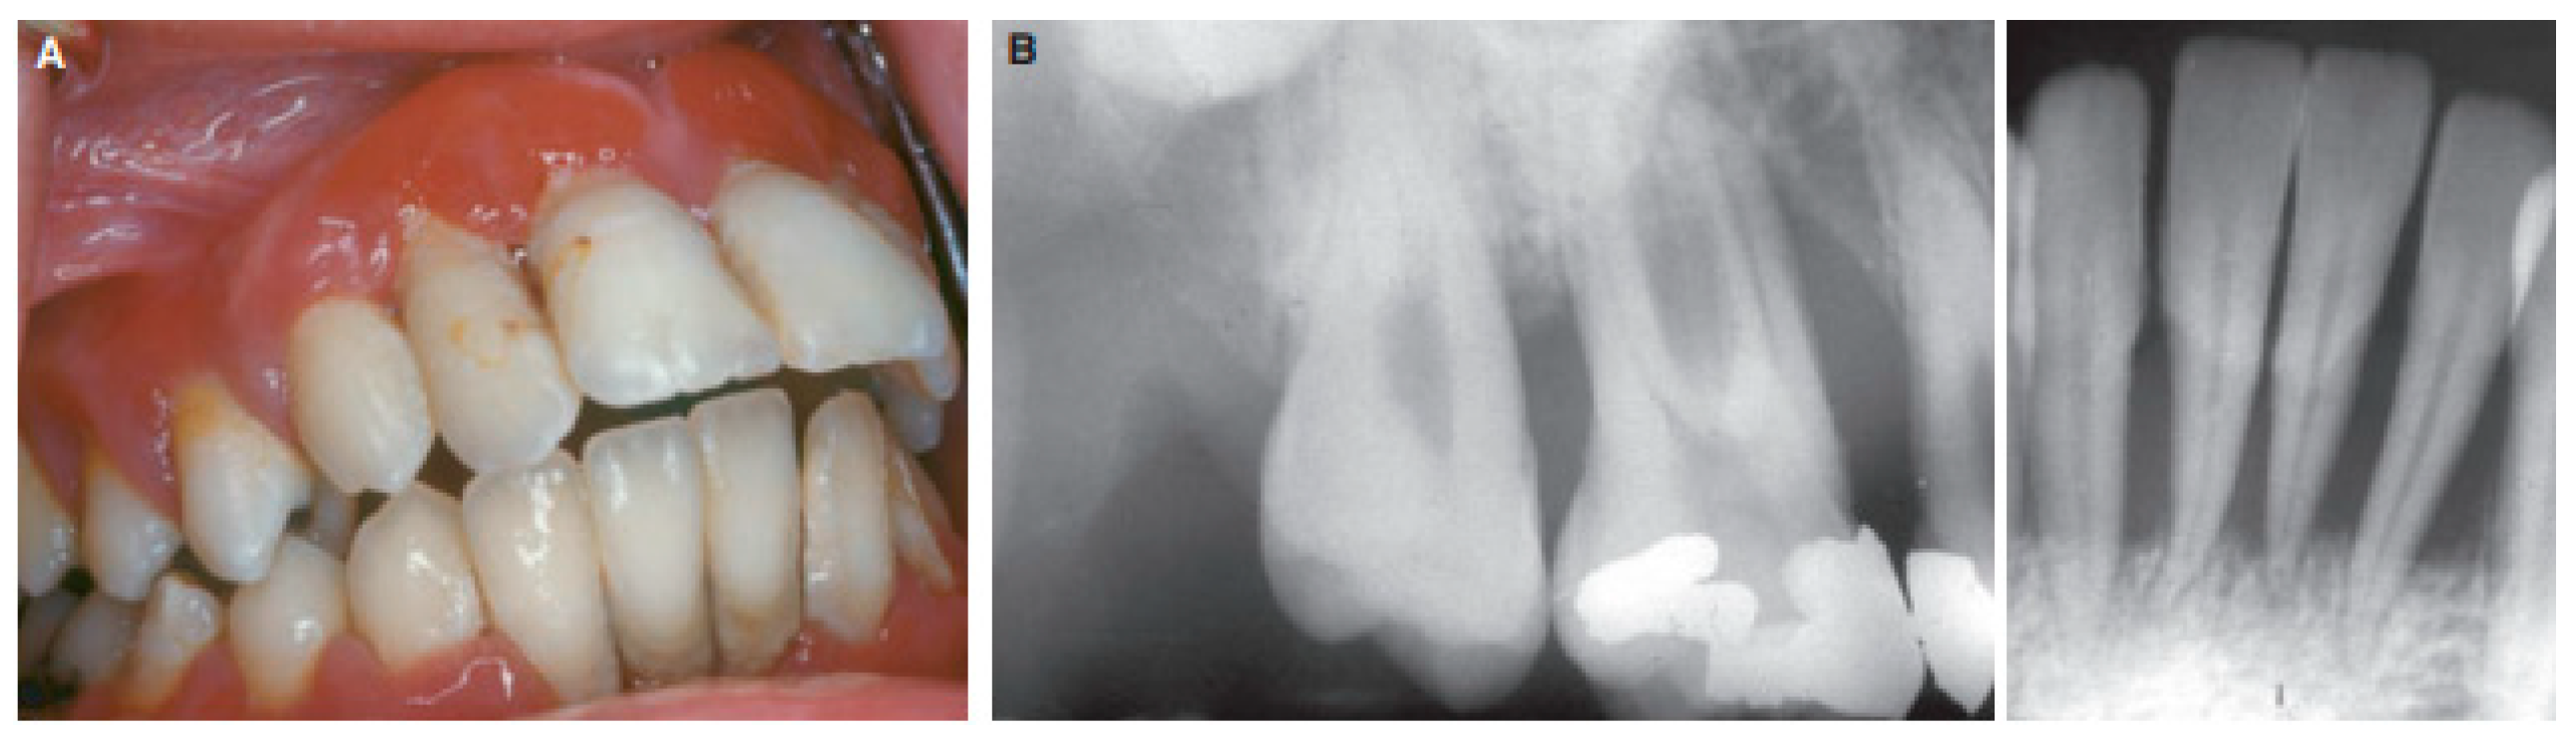

Oral cancer

- Almangush, A.; Pirinen, M.; Heikkinen, I.; Mäkitie, A.A.; Salo, T.; Leivo, I. Tumour budding in oral squamous cell carcinoma: a meta-analysis. British journal of cancer 2018, 118, 577–586. [Google Scholar] [CrossRef]